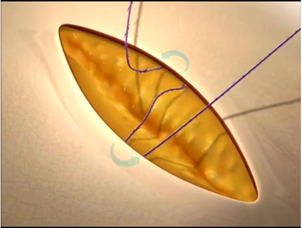

中国医科大学附属第一医院肾内科采用可吸收蛋白线或者倒刺线进行美容缝合,缝合方式如图2。

图 2 采用倒刺线的美容缝合方法,图片来自于快翎quill网站。